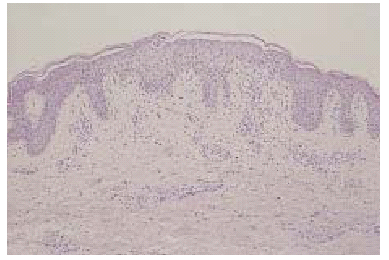

Un varón de 35 años de edad, con antecedentes de seminoma testicular con orquiectomía derecha en mayo de 1997, desarrolló en marzo de 1998 metástasis pulmonares que respondieron a tratamiento con 3 ciclos de BEP (bleomicina, etopósido y cisplatino). Dos años después fue diagnosticado de una leucemia mieloide M4 bifenotípica (linfo/monocitaria), con cariotipo de mal pronóstico [46XY 11q-, t(7,14)], secundaria muy probablemente a etopósido. Recibió tratamiento de inducción con citarabina e idarubicina, sin obtener respuesta. Posteriormente alcanzó la remisión completa con FLAG-Ida (fludarabina, adriamicina, dexametasona e idarubicina). En septiembre del 2000 se le realizó un trasplante alogénico de médula ósea procedente de un hermano con antígeno de histocompatibilidad (HLA) idéntico, previo acondicionamiento con fludarabina y melfalán. El donante presentaba dermatitis atópica, sin otros antecedentes de interés. La profilaxis inicial de EICH se realizó con ciclosporina y metotrexato. El paciente no presentó datos de EICH aguda y fue dado de alta con ciclosporina A, en dosis de 500 mg/día como único inmunodepresor. Se realizó un estudio de médula ósea, que fue normal, y dado que el paciente presentaba buen estado general, sin signos clínicos ni analíticos de EICH, al mes del trasplante se fue reduciendo de forma progresiva la dosis de ciclosporina. A los 50 días del trasplante mientras recibía una dosis de ciclosporina A de 200 mg/día, presentó un exantema maculopapuloso pruriginoso en la zona del escote, espalda y superficie de extensión de extremidades. Se realizó una biopsia cutánea del antebrazo, que mostró marcada espongiosis, exocitosis y formación de vesículas espongióticas (fig. 1). En la dermis papilar existía un marcado infiltrado inflamatorio perivascular superficial con presencia de macrófagos aislados. Se estableció el diagnóstico anatomopatológico de dermatitis espongiótica. No se observaron dermatitis de interfase ni queratinocitos necróticos. Ante este resultado histológico, y considerando que el donante era atópico se realizó determinación sérica IgE, que fue normal. Puesto que el paciente persistía con buen estado general, afebril, sin disnea, diarrea, dolor abdominal, ni otra sintomatología, y el estudio analítico, incluyendo el perfil hepático, no presentaba alteraciones significativas, se continuaron disminuyendo las dosis de ciclosporina A. Así, a los 65 días postrasplante, mientras tomaba una dosis de 100 mg/día, empeoraron las lesiones cutáneas, que afectaban ya a más del 80 % de la superficie corporal. En la exploración física presentaba (figs. 2 y 3) un gran número de pápulas de aspecto liquenoide, de distribución extensa por espalda, extremidades inferiores, cara anterior del tronco y, sobre todo, en miembros superiores, con afectación intensa del dorso de las manos. También se encontraron lesiones liquenoides en mucosa oral, en forma de reticulado blanquecino en ambas mucosas yugales. El paciente persistía con buen estado general, afebril, sin disnea, diarrea, ni otra sintomatología. El perfil hepático en este momento mostraba transaminasas glutamicooxalacética (GOT) de 676 U/l; glutamicopirúvica (GPT), 1.075 U/l, y gammaglutamiltranspeptidasa (GGT), 830 U/l; fosfatasa alcalina, 947 U/l, y bilirrubina, 2,5 mg/100 ml. Se realizó una nueva biopsia cutánea del dorso de la mano, que mostró una dermatitis de interfase con necrosis queratinocítica y degeneración vacuolar basal epidérmica y folicular, compatible con EICH (fig. 4). Con estos datos, el paciente fue diagnosticado de EICH aguda cutánea de grado 3 y hepática de grado 1. Se instauró tratamiento con prednisona, en dosis de 2 mg/kg/día, ácido ursodesoxicólico y ganciclovir profiláctico y se aumentaron las dosis de ciclosporina A a 500 mg/día. El paciente presentó una mejoría progresiva del cuadro cutáneo y hepático, con lo que se inició nuevo descenso progresivo de la inmunosupresión, con buena respuesta, sin aparición de nuevos signos de EICH hasta la actualidad.

Fig. 4.--Detalle de imagen histológica: dermatitis de interfase con marcada degeneración vacuolar y borramiento de la basal epidérmica. Nótese la presencia de aislados queratinocíticos necróticos intraepidérmicos (hematoxilina-eosina).